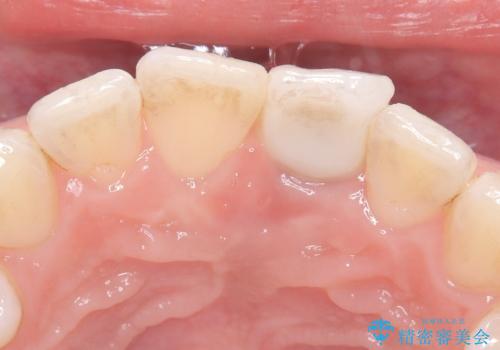

- 歯頚部外部吸収により抜歯適応の歯を抜歯して即時にインプラントを埋入したケースです。

歯肉が下がっていることを気にされていたため、できるだけ考慮して術式を決めて治療を行いました。